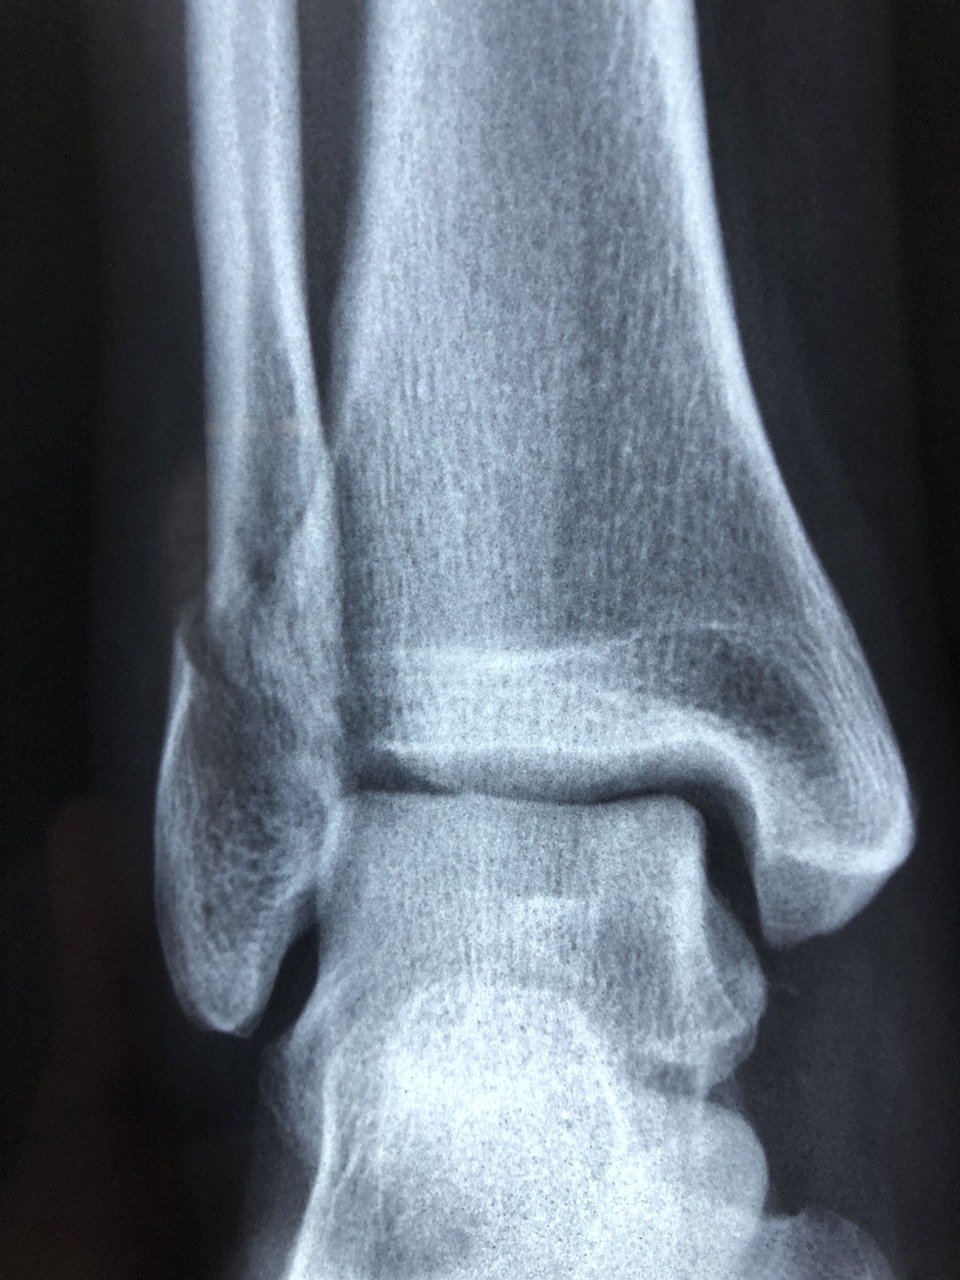

5. X-선 촬영: 발목의 뼈에 손상이 있는지 확인하기 위해 X-선 검사를 실시할 수 있습니다.